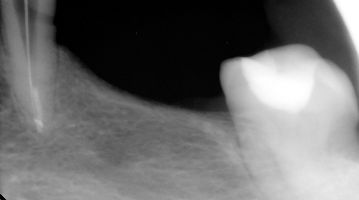

Ząb - lewa dolna czwórka. Bolał po leczeniu kanałowym. Podjęto decyzję o leczeniu pod mikroskopem. Odnaleziono i udrożniono drugi kanał korzeniowy. Dolegliwości ustąpiły.